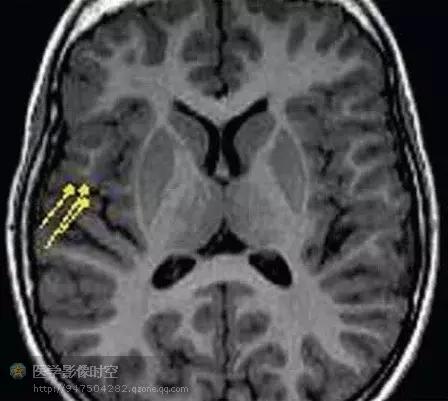

图2 a b 3岁男孩Ⅱ型局部皮质发育不良。

图2a横断T2WI显示局部灰白质交界区模糊(箭头所示)及右侧额下回异常T2高信号影(箭)。

目前的影像学检查方法,包括磁共振成像,磁源成像,或者PET尚不能可靠的鉴别轻度皮质发育不良,局部皮质发育不良Ⅰ型和Ⅱ型(图1-6)。但是,如果发现皮层下T2高信号,尤其是延伸到侧脑室,常常是ⅡB型(图2)。目前认为T2高信号是髓鞘化程度低造成的,而非气球样细胞所致。其它的局部皮质发育不良的典型磁共振成像表现包括局部皮质增厚,灰白质界限模糊,灰质高信号(图6)。